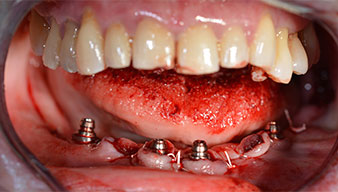

L’extraction de la denture résiduelle à la mandibule a exposé la crête alvéolaire de 37 à 47.

Le trou mentonnier doit d'abord être identifié comme une structure anatomique limitante, puis l'os cortical de la crête a été régularisé avec une pièce à main droite et une fraise sphérique de grande taille (Fig. 4).

Un CT Scan à faisceaux coniques tridimensionnel (CBCT, Planmeca) a été réalisé au préalable afin de réduire les risques. Il a révélé une qualité et une quantité d'os disponible suffisante pour l'intervention chirurgicale et la restauration immédiate par la méthode All-on-four. En suivant le protocole de ce concept, les implants sont insérés au niveau de 35, 32, 42 et 45 en inclinant les implants distaux jusqu'à 45°, le profil d'émergence se déplace ainsi vers l'arrière et produit un polygone de stabilisation plus large (Fig. 3).